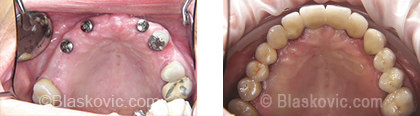

3. Most umjesto totalne proteze

Čak i u slučaju potpune bezubosti implantati nude rješenje. Ugradnjom minimalno 4 do 6 implantata dobivamo nosače za fiksni most koji u ustima stoji fiksno zacementiran, bez potrebe za svakodnevnim vađenjem.